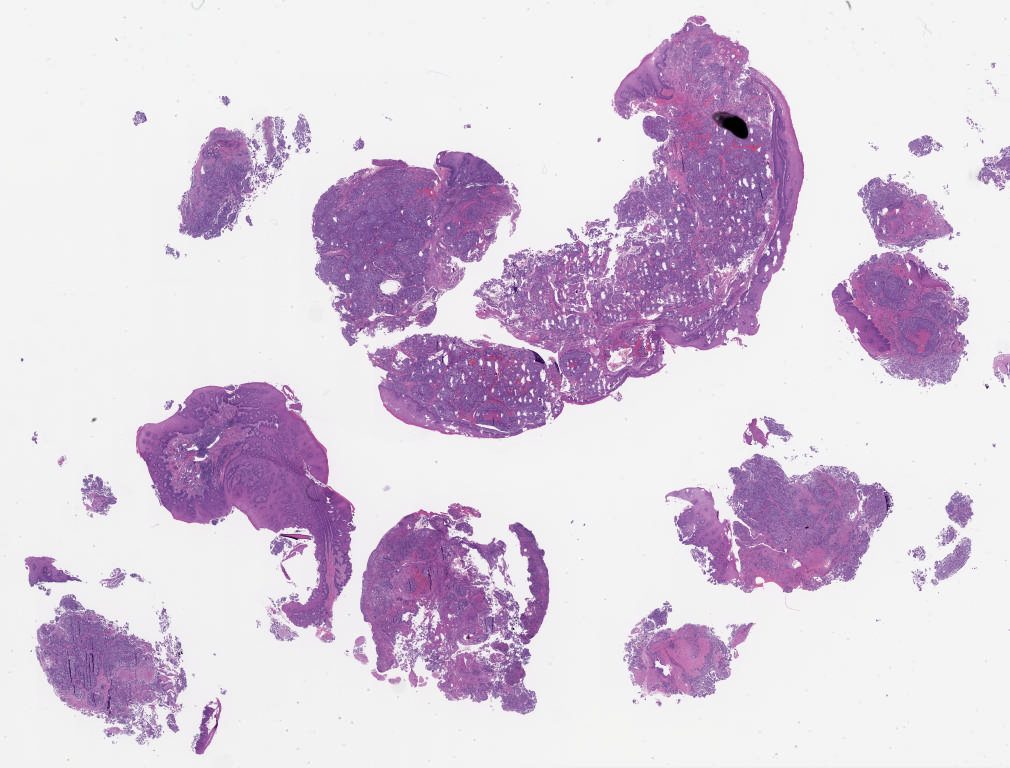

University of Pittsburgh Oral Pathology Study Set Summer 2025\Case01

1841673.svs